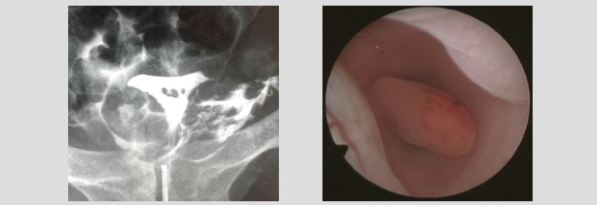

It is very important to perform a thorough evaluation of the endometrial cavity, fibroids, polyps, including micro polyps, are common causes of implantation failure. The presence of any of these conditions, regardless of size and location, have the potential to generate a change in the endometrial enviroment preventing an adequate communication between the embryo and the endometrium for implantation to occur.

There are other important conditions such as the evaluation of thin endometrium, which is commonly associated with synechiae, that prevent the proper development of the endometrium, including small synechiae in the isthmus. The opposite is also true, as in the evaluation of thickened endometrium where it is important to take a biopsy under direct visualization of the most abnormal looking area. Of note, in this pathology can coexist in the same patient lesions with atypia and focal lesions without atypia making the specific biopsy site very important for an accurate diagnosis. It is a consensus that edometrial stripes smaller than 6mm or greather than 14mm, are not suitable for nesting pregnancies.

Finally, in the diagnosis of chronic inflammatory conditions of the endometrium (endometritis), hysteroscopy has well-established diagnostic criteria, which allow 93% accuracy. Chronic endometritis is a known cause of implantation failure. Asymptomatic cases can only by diagnosed by endometrial biopsy and hysteroscopy if done as routine. Blind endometrial biopsy has diagnostic limitations, but hysteroscopic view of this condition enables the diagnosis even without pathological anatomical correlation.